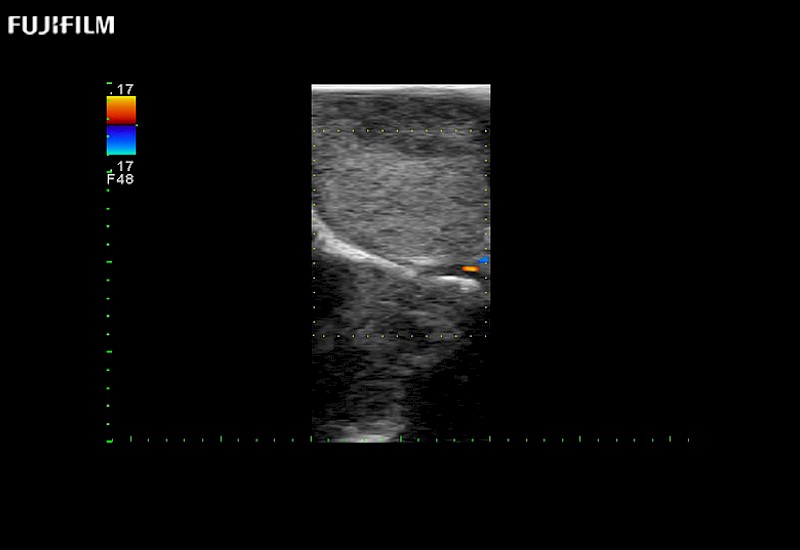

Exclusive 10mm side‐fire linear array transducer with 2.87mm diameter is ideal for real‐time visualization through and behind structures and instant, scalable definition of anatomy and vascularity including the ability to delineate and define tumor margins.

Main Specifications: